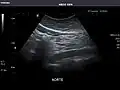

Abdominal Ultrasound (Full Exam)

STRUCTURED REPORT

(Technique: Transabdominal ultrasonography; Device: Toshiba Aplio XG)

Aorta: Visualized portions normal in caliber, 16 x 15 mm.

Aorta -